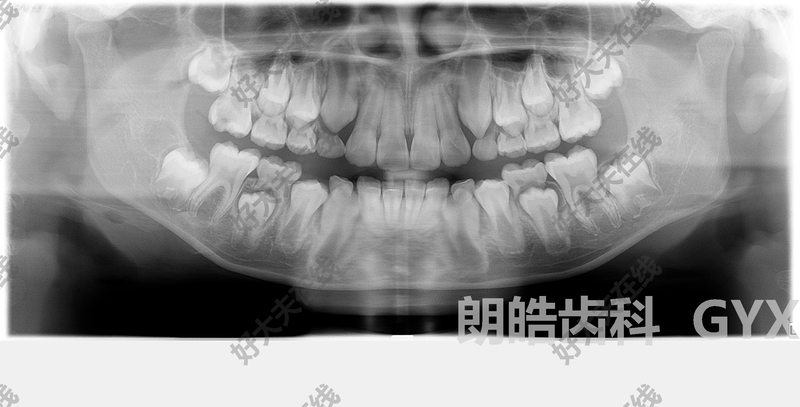

看了這張圖,還敢說乳牙蛀牙不用補?

有老觀點認為“乳牙蛀了不用補,等著換牙就好了",殊不知嚴重的乳牙蛀牙也會影響恒牙。兒童齲齒預防大于治療,家長們要注意孩子的口腔衛(wèi)生,每天2-3次刷牙,每次2分鐘,6周歲以下的兒童需要家長幫忙刷牙。兒童需每3個月或6個月到口腔科做全面檢查,及時做涂氟,窩溝封閉等預防齲齒。